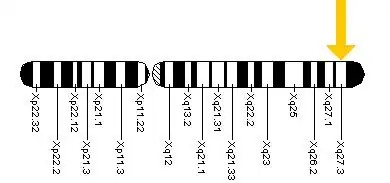

Fragile X-associated tremor/ataxia syndrome (FXTAS) is a late-onset neurodegenerative disorder most frequently seen in male premutation carriers of Fragile X syndrome (FXS) over the age of 50.[6][7] The main clinical features of FXTAS include problems of movement with cerebellar gait ataxia and action tremor.[6][8] Associated features include parkinsonism, cognitive decline, and dysfunction of the autonomic nervous system.[6][8] FXTAS is found in Fragile X "premutation" carriers, which is defined as a trinucleotide repeat expansion of 55-200 CGG repeats in the Fragile X mental retardation-1 (FMR1) gene.[9] 4-40 CGG repeats in this gene is considered normal, while individual with >200 repeats have full Fragile X Syndrome.[9]

The etiology of Fragile X-associated tremor/ataxia syndrome, has a mutation known as a CGG triplet repeat, which occurs within the FMR1 gene[11]